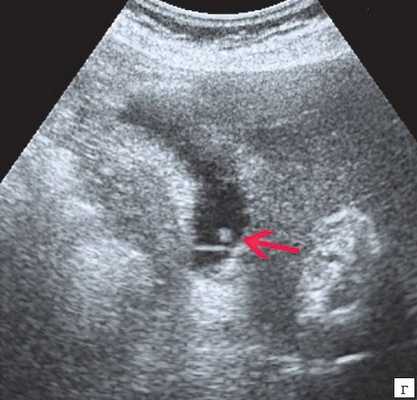

(Левый) Пример неполного кальциноза: у женщины 67 лет, жалующейся на боли в правом верхнем квадранте живота после еды определяются отдельные гиперэхогенные очаги передней и задней стенок желчного пузыря, отбрасывающие неоднородную тень.

(Правый) Пример неполного кальциноза: у мужчины 61 года в стенке желчного пузыря визуализируются точечные кальцинаты. Выявленные при патологоанатомическом исследовании конкременты не визуализируются.